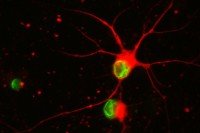

Seeing the Light: How Engineered Nerve Cells Might Curb Parkinson’s Disease

A new tool called optogenetics is revealing clues about the function of a promising experimental therapy derived from stem cells.

In the Lab